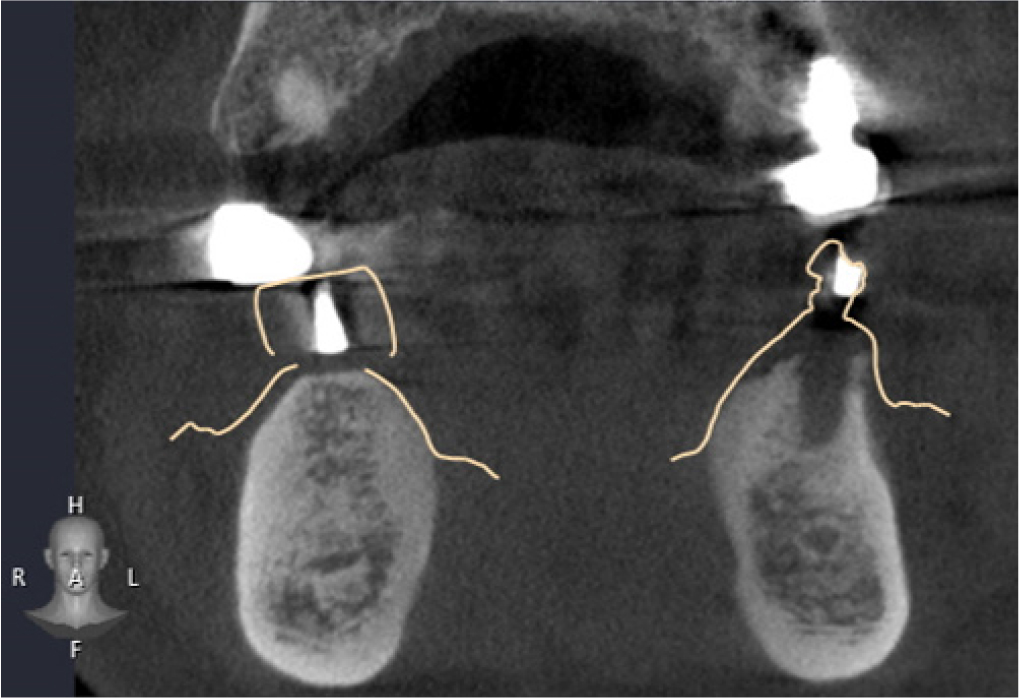

DentalCAD 2.3 (Exocad GmbH; Darmstadt, Germany) program was used to superimpose radiographic stent model scan data with model scan data, and then both files were loaded on DentiqGuide software. DICOM files from CBCT data and radiographic stent model scan data were superimposed on DentiqGuide software using gutta-percha (Temporary stopping; GC Corporation, Tokyo, Japan) to match the model scan data with CBCT data (Fig. 4). In addition, to confirm that the model scan data and CBCT data matched accurately, we checked whether the gingiva line of the model and the bone line of CBCT matched the software and whether the location of the gutta-percha in the model and CBCT matched (Fig. 5). Implant planning and surgical guide design were performed by referring to the CBCT and model scan data, and the surgical guide was printed using a DLP (Digital Light Processing) type 3D printer (Zenith D; Dentis, Daegu, Korea) (Fig. 6). The lower left canine root is tilted mesially. Therefore, when working with the planning software, placing the implant on the adjacent lateral incisor was difficult, and the cantilever was planned after placement on the central incisor.

In this case, it was difficult to ensure perfect superimposition because there were insufficient markers other than gutta-percha. Because the accuracy of superimposition is the key to the precision of guided surgery, a process to reconfirm it is needed. In the superimposed CBCT cut view of the radiographic stent model scan and CBCT data, the fit of the thin part of the gingiva was checked, and it was confirmed that there was no place where the boundary of the bone deviated from the boundary of the model in all parts. In addition, the gutta-percha in the CBCT data coincided with that in the optical model scan data. One limitation of this method is that it cannot be used unless there is a function to load additional optical scan data into the guide design software.